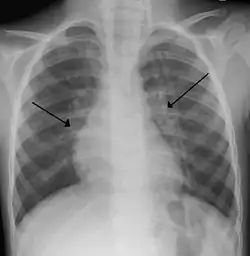

التهاب القصيبات

التهاب القصيباتللرئتين والمسماة القصيبات وهو يختلف عن التهاب القصبات الكبيرة،. وعادة ما يحدث في الأطفال الذين عمرهم أقل من سنتين من وبالاخص اغلب الحالات تصيب الذين تتراوح أعمارهم بين بين ثلاثة وستة أشهر.[2] حيث تكون لديهم الممرات الهوائية أصغر من الرئتين. سبب هذا الالتهاب فيروسات واهما فيروس المخلوي التنفسي (فيروس ر س ف)(70٪ من الحالات).[3] وفيروسات اخرى مثل فيروس الباراانفلونزا والانفلونزا والادينوفيروس .ويؤدي التهاب القصيبات إلى التهاب وتوذم في القصيبات وصفير وسعال وضيق التنفس الذي يمكن أن يسبب بعض الصعوبة في تغذية الأطفال. وأكثر انتشاره يكون في موسم الشتاء.